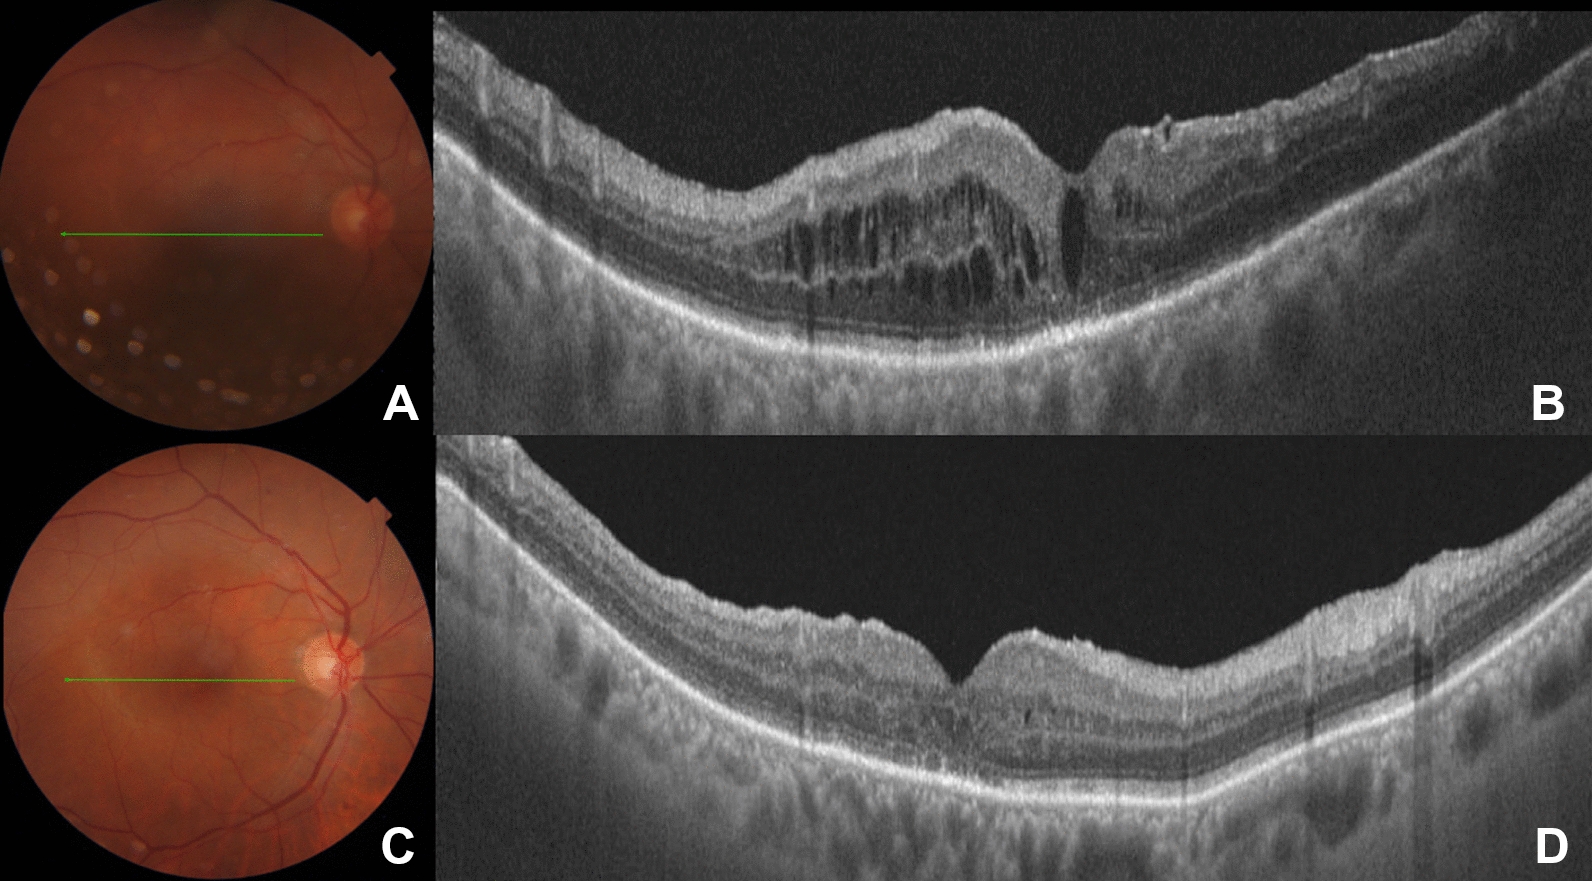

A representative case of chronic CSC successfully treated with YSML is shown in Fig. 1.

Multimodal imaging of a 41-year-old patient with an 11-month history of chronic central serous chorioretinopathy (cCSC) treated with yellow subthreshold micropulse laser (YSML). AB Baseline color fundus photography (A) and red-free light picture (B) show neurosensory retinal detachment in the macular area. CD Early and late phase fluoresceine angiography displays the characteristic ink-blot pattern with a single point leakage that gradually increases in size over time. The area of leakage (red circle, D) is the target of YSML. EG Tracked spectral domain optical coherence tomography scans with corresponding near infrared images acquired with enhanced depth imaging mode at baseline (E) and at 1 month (F) and 6 months (G) after YSML show resolution of the subretinal fluid over time

A representative case of postsurgical CME successfully managed with a single YSML session in a patient operated on for a rhegmatogenous retinal detachment is shown in Fig. 2.

Persistent post-surgical macular edema following a combined cataract and pars plana vitrectomy (PPV) surgery for rhegmatogenous retinal detachment (RD) successfully treated with yellow subthreshold micropulse laser (YSML). A Color fundus picture 3 months after combined cataract and PPV surgery for rhegmatogenous RD shows a reattached retina. B Spectral domain optical coherence tomography (SD-OCT) image shows persistent intraretinal cysts not responsive to any topical and/or oral medications including anti-inflammatory and steroids eye drops. C Color fundus picture 6 months after YSML session. D Corresponding tracked SD-OCT reveals resolution of the intraretinal fluid